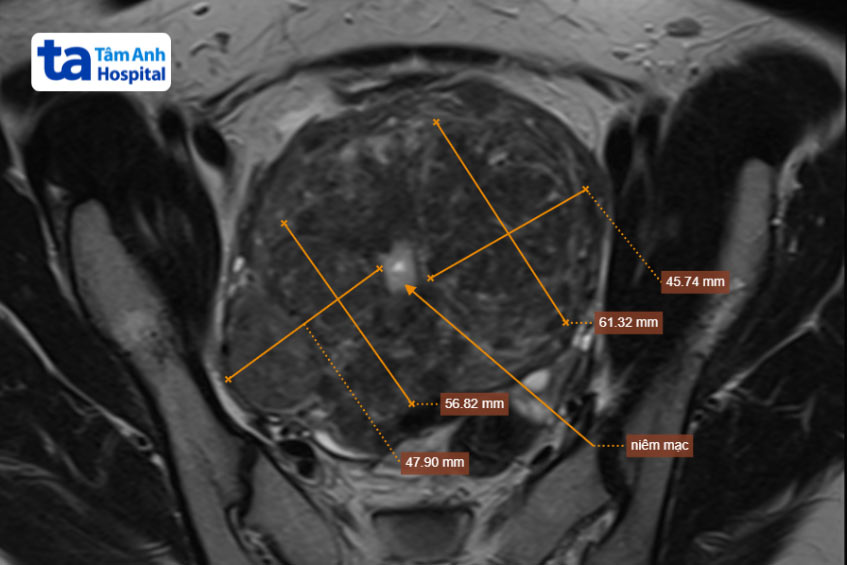

Tháng 7/2023, chị đến khám tại Trung tâm Chẩn đoán hình ảnh và Điện quang can thiệp BVĐK Tâm Anh Hà Nội. TTƯT.PGS.TS Nguyễn Xuân Hiền, Giám đốc Trung tâm, cho biết hình ảnh chụp cộng hưởng từ cho thấy u lớn nhất 64mm, nhỏ nhất 2-3 mm, liên kết như chùm nho, ước tính có khoảng trên 10 u. Các khối u xơ lấp đầy toàn bộ lòng tử cung, chỉ còn 10% là niêm mạc lành, tử cung biến dạng khiến người bệnh khó thụ thai và giữ thai.